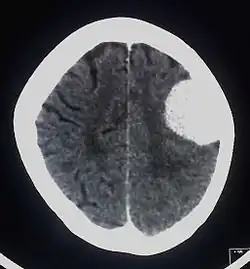

Oponiak (łac. meningioma) – zazwyczaj łagodny (w 90% I° według WHO) nowotwór ośrodkowego układu nerwowego, zwykle łatwy do zoperowania, umiejscowiony w oponach mózgowo-rdzeniowych mózgowia lub rdzenia kręgowego. Oponiaki są najczęstszymi łagodnymi nowotworami mózgu.

Większość zmian zlokalizowana jest poza miąższem mózgu, wewnątrz czaszki lub kanału kręgowego. Guzy mają postać twardych mas dobrze odgraniczonych od przylegającego mózgu, przytwierdzonych do opony twardej. Możliwy jest naciek kości czaszki. Niekiedy w guzie obecne są zwapnienia (ciałka piaszczakowate). Większość zmian jest mała (poniżej 2 cm).

Najczęstszym objawem jest wzrost ciśnienia wewnątrzczaszkowego mogący prowadzić do napadów padaczkowych a także wywoływać ogniskowe objawy neurologiczne zależne od umiejscowienia guza (notowano np. przypadki porażenia spastycznego kończyn dolnych spowodowanego obecnością oponiaka). Większość małych guzów nie daje żadnych objawów. Możliwe są nawroty po chirurgicznym lub radiologicznym usunięciu, ale niemal wszystkie oponiaki są zmianami łagodnymi, złośliwienie jest wyjątkowo rzadkie.